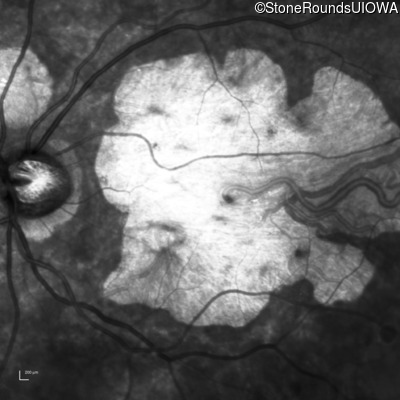

Age at visit: 43 years

OD OS